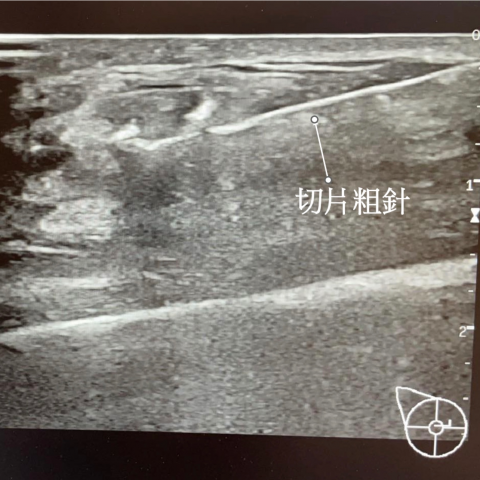

乳房硬塊切片檢查

【陳尹陽醫師|乳房外科臨床案例】乳房超音波追蹤:為什麼看起來小小一顆,也可能要切片? 案例分享:0.3 公分的小腫瘤,半年後為什麼立即建議切片? 這位患者半年前在外院做乳房超音波,發現一顆 0.3 公分的小腫...